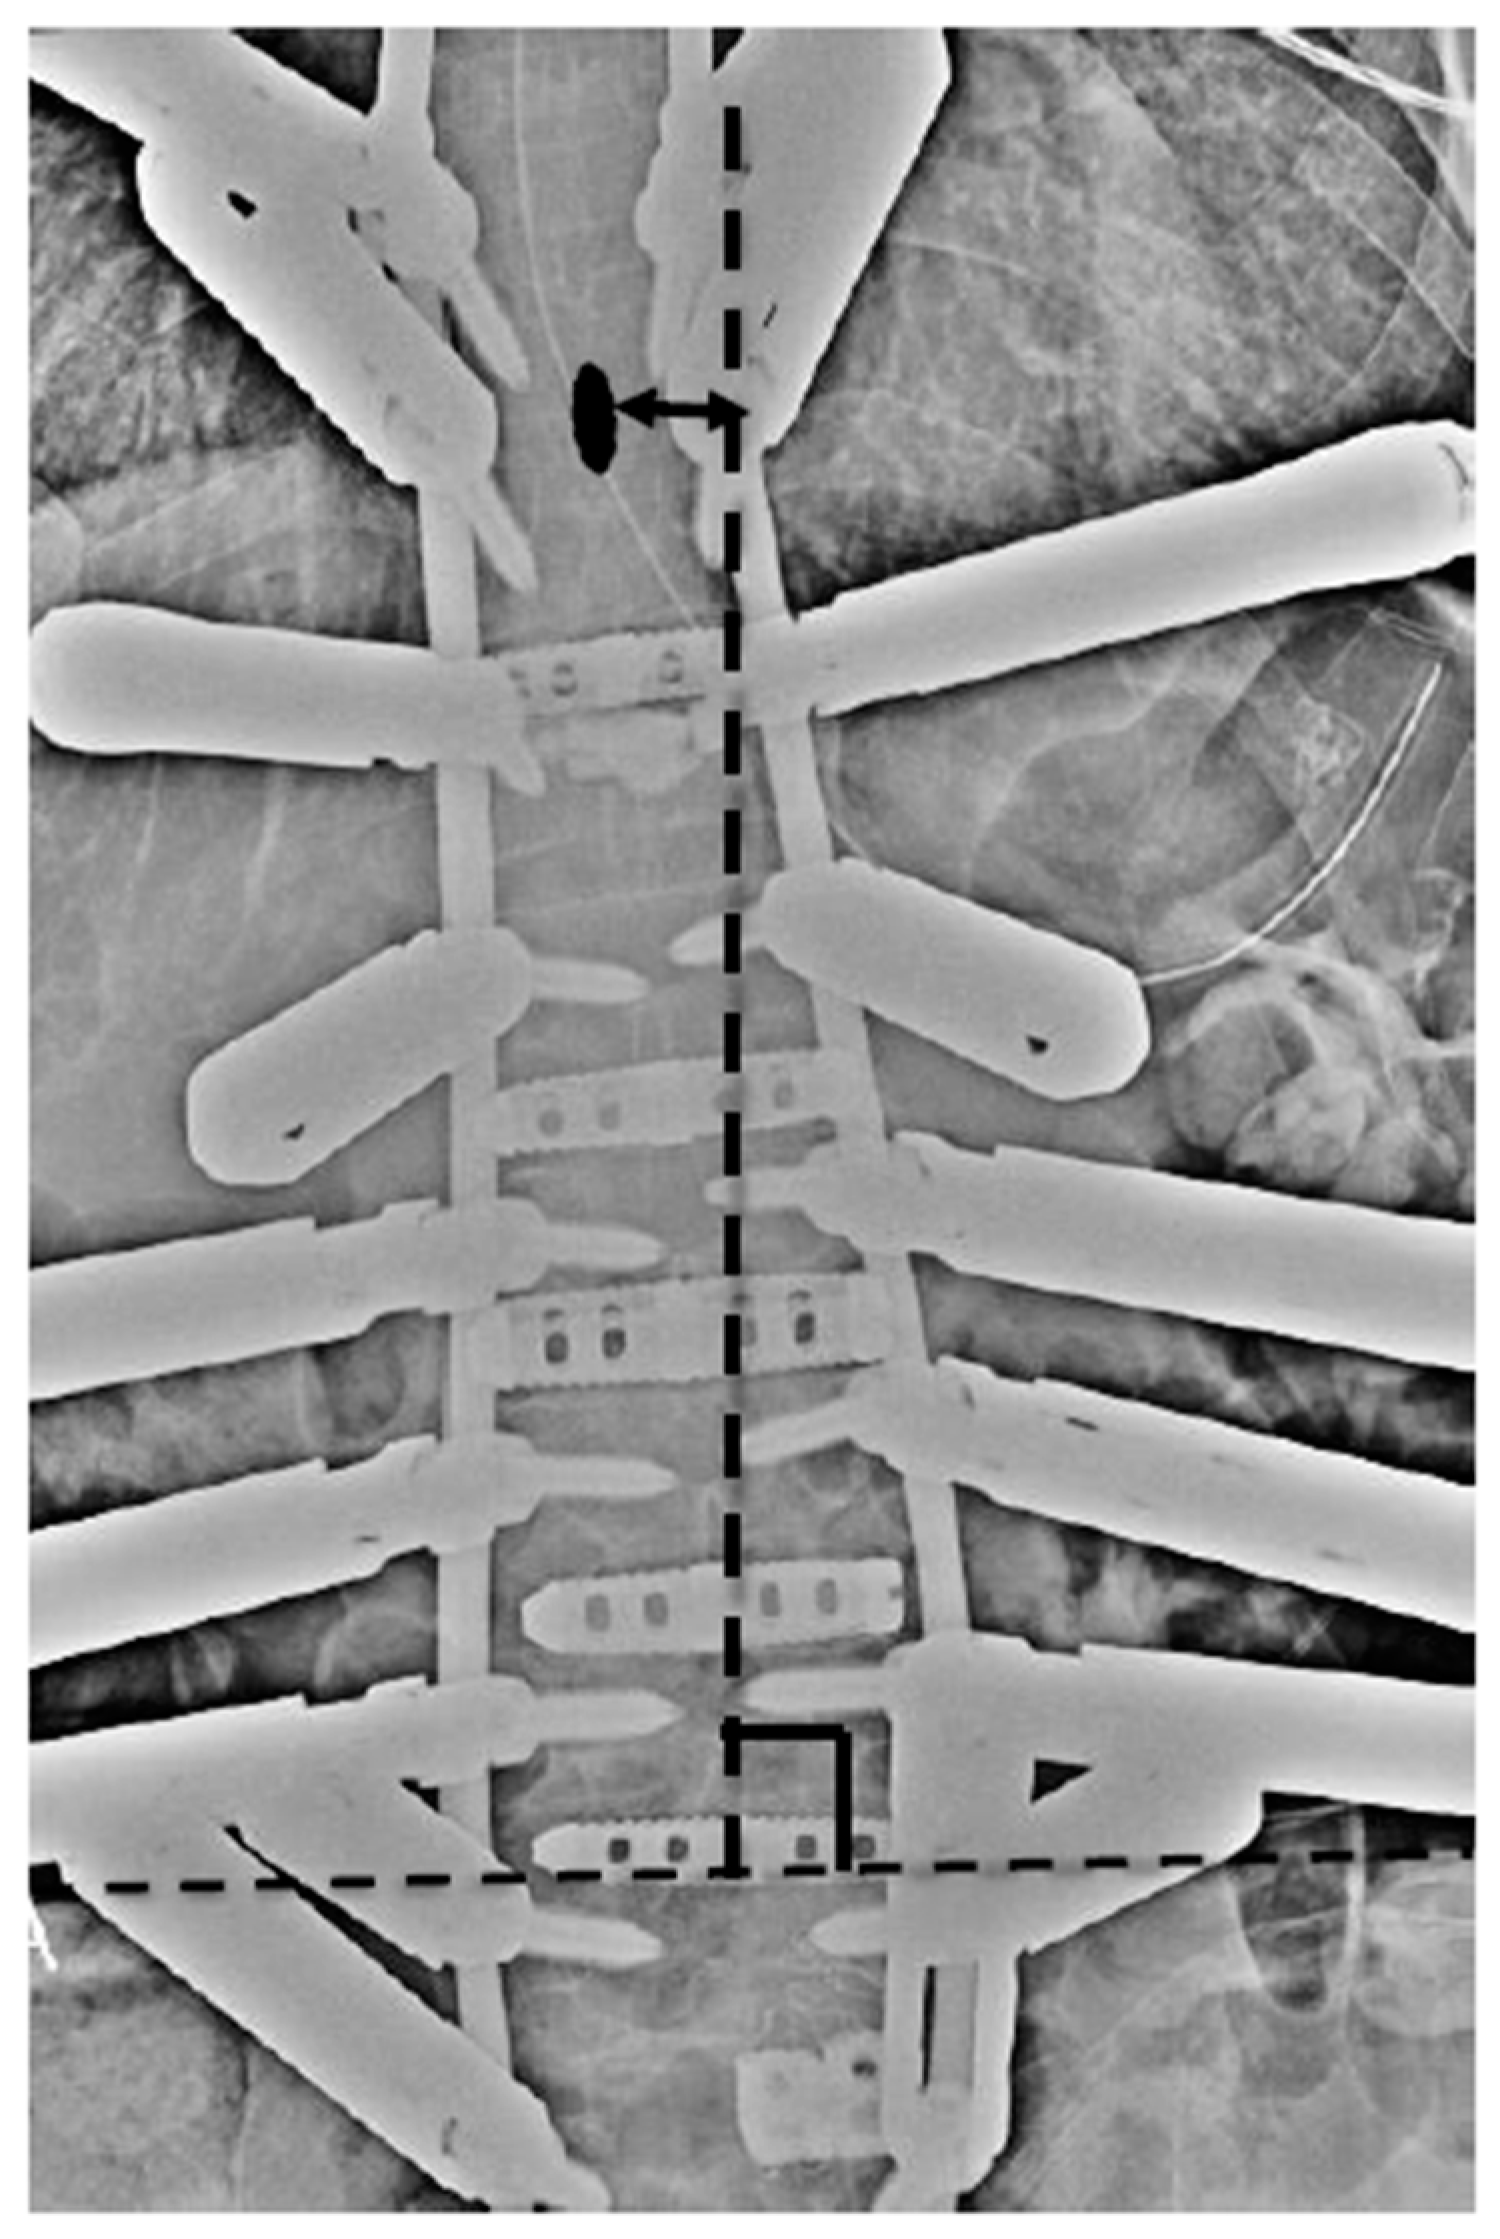

3.1. Case Study 1: RR